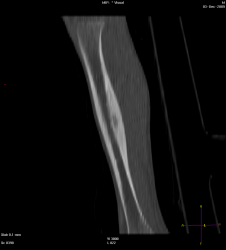

Мальчик 8 лет, был направлен травматологом к нам, с жалобами: на ноющую боль в голени в течении 2 мес., преимущественно усиливающася в ночное время, но проходящая после приёма НПВС. Провели МСКТ:

Думаю, что большого труда не составит определиться, что это за патологическое состояние, хоть и был отход от "классики". Случай ещё пока не верифицирован!

Остеоид-остеома. А в чем отход от классики?

Диф.ДЗ с первично-хроническим остеомиелитом.

Интересное наблюдение, но для "классики" остеоид - остеомы не хватает - пуговки - подобия секвестра в полости, но это в любом случае хронический остеомиелит подлежащий оперативному лечению.